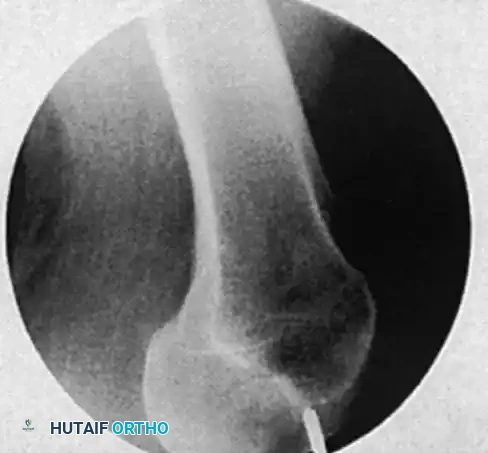

1. Obtaining Perfect Circles: Position the C-arm for a lateral view of the distal femur. Adjust the C-arm trajectory until the distal interlocking holes of the nail appear as perfect, crisp circles. If the holes appear oblong, elliptical, or exhibit a "double density" crescent, the C-arm is not perfectly orthogonal to the nail. Adjust the tilt and rotation until perfect circles are achieved.

2. Incision: Center the tip of a scalpel or a radiopaque ring forceps over the chosen interlocking hole on the lateral aspect of the thigh. Make a longitudinal stab incision through the skin, subcutaneous tissue, and the dense iliotibial band.

3. Awl/Drill Positioning: Place a trocar-tipped drill bit or a radiolucent awl into the incision, resting on the lateral cortex. Angle the handle approximately 45 degrees to the fluoroscopic beam. This angulation keeps the surgeon's hands out of the direct radiation field while allowing clear visualization of the tip.

Image

Freehand technique: The awl is placed over the proximal screw hole with its handle angled 45 degrees to avoid radiation exposure to the hands.

The awl is meticulously adjusted under continuous image intensification until the point is perfectly centered within the screw hole.

1. Drilling: Once the tip is perfectly centered in the hole, swing the drill perpendicular to the axis of the bone, bringing it parallel and directly in line with the fluoroscopic beam.

The awl is swung perpendicular to the axis of the bone, aligning perfectly with the trajectory of the interlocking hole.

The awl is driven through the lateral cortex and into the nail.

1. Maintain constant, firm pressure to prevent the drill tip from skiving off the hard diaphyseal bone. Penetrate the lateral cortex.

2. Remove the drill bit from the power driver. Take a lateral fluoroscopic image to confirm that the drill bit is passing directly through the interlocking hole of the nail.

3. Reattach the driver and drill through the medial cortex.

4. Measurement and Insertion: Use a calibrated drill bit or a standard depth gauge to determine the required screw length. Insert the interlocking screw by hand, confirming satisfactory cortical purchase.

5. Repeat the process for the second distal interlocking screw to ensure maximum rotational control.

Fluoroscopic confirmation of distal interlocking screw placement, ensuring adequate length and bicortical purchase.